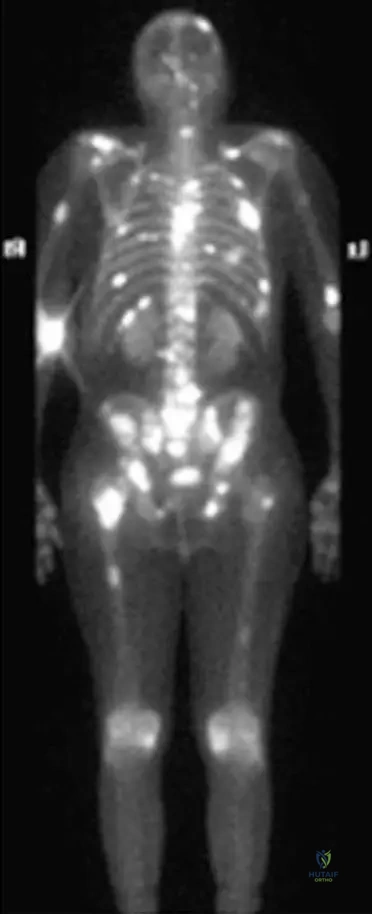

Question 86

A 70-year-old male with a known history of prostate cancer presents with new onset diffuse bone pain. A technetium-99m bone scan is performed, revealing multiple areas of increased radiotracer uptake throughout the axial skeleton, consistent with the image provided. What is the most likely characteristic of these metastatic lesions from prostate cancer?

View Answer & Explanation

Correct Answer: C

Rationale: The image (Fig. 8.122) is a bone scan of multiple bony metastases from prostate carcinoma, showing increased uptake. Increased uptake on a bone scan typically indicates osteoblastic activity, which corresponds to blastic (radiodense) lesions on plain radiographs. While the text states radiographic appearance is variable, prostate cancer is classically associated with blastic metastases. Purely lytic (A) is less common for prostate, and soft tissue masses without bone involvement (D) would not show increased uptake on a bone scan.